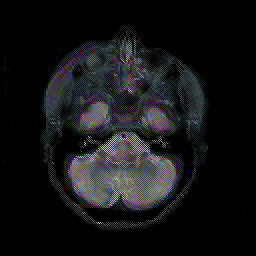

Glioblastoma multiforme overlay -- Slice #14

[Home][Help][Clinical][Tour 1][Tour 2][Tour 3] Slice 14